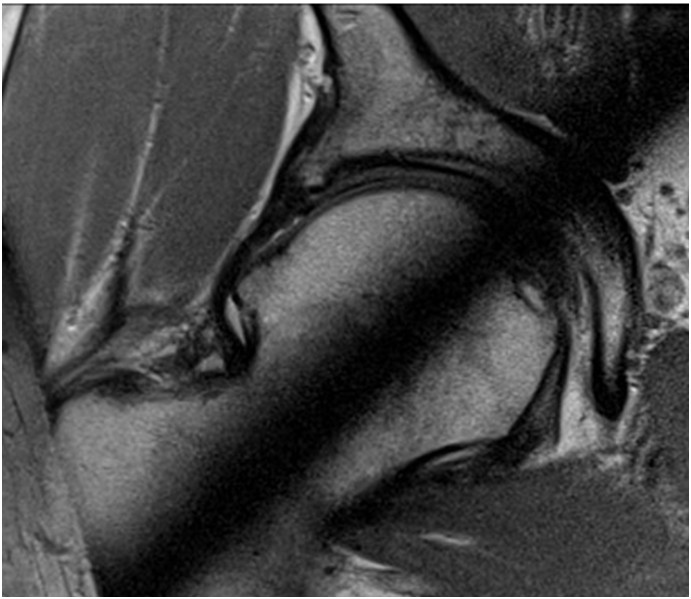

22-letni mężczyzna odczuwa ból obu bioder, z przewagą po stronie lewej, dotychczas uprawiał sport. Klinicznie: stwierdza się ograniczony zakres ruchów, z pomniejszeniem zgięcia, przywiedzenia i rotacji wewnętrznej. Wskaż prawidłowe rozpoznanie:

Pytanie 38